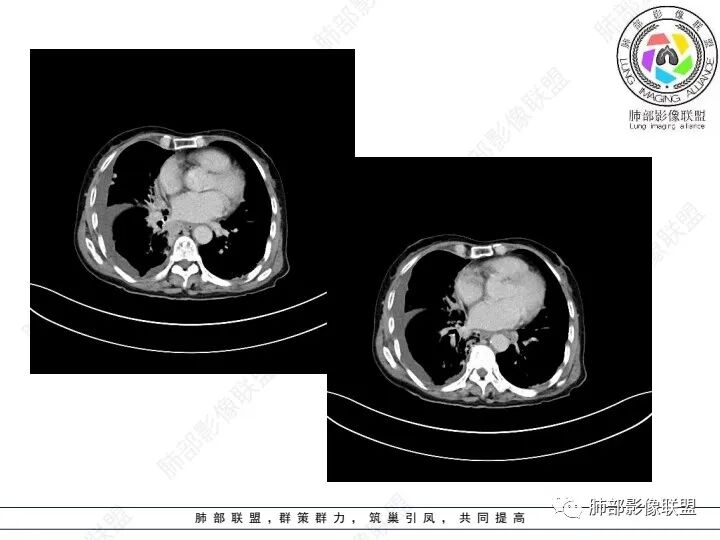

右肺下叶胸膜下不规则肿块,与肺门相连,不均匀强化,胸壁受侵,右肺内多发小结节,下叶血管束增粗,小叶间隔增厚,右肺门及纵膈多发淋肿大淋巴结,融合,右侧胸水,考虑腺癌转移

患者老年女性,腹痛、黑便4小时。查肿瘤结果CA125明显升高,余正常。胸部CT:双肺胸膜下间质性改变,右肺胸膜下多发结节灶,以右肺下叶为大,增强渐进性强化,内低密度灶。右肺门淋巴结肿大伴钙化,右中间支气管狭窄,右侧包裹性胸腔积液。综合考虑恶性,腺癌可能大。鉴别转移。

右肺下叶胸膜下肿块,密度不均,不均匀强化,胸膜栽赃,右肺多发小结节,右肺门及纵膈多发淋肿大淋巴结,下叶支气管受压变窄,右侧胸水,考虑恶性,腺癌转移。

右肺下叶占位,右肺下叶支气管狭窄,周围见软组织密度结节包饶,增强结节病灶强化不明显,右肺胸膜下见多个结节影,考虑恶性病变,低分化腺癌可能

老年女性,以消化道出血入院,右肺下叶靠近脊柱旁肿块,边缘毛糙,有栽赃,内有坏死,胸膜多发结节,右侧胸腔积液,同侧肺门纵隔多发肿大淋巴结,考虑恶性肿瘤可能,不知是一元还是二元,一元消化道肿瘤肺转移?或者二元肺部肿瘤胸膜转移,肿瘤标志物不是很高,考虑间皮瘤?淋巴瘤?

右下肺实变影,周围模糊,均匀强化,内可见低密度坏死,局部胸膜肥厚粘连,胸腔积液,纵隔淋巴结肿大,恶性肿瘤要首先排除。

老年女性,肺气肿背景。腹痛、便血入院。右肺下叶脊柱旁软组织肿块,强化不均匀,中心有坏死,纵隔及双侧肺门多发肿大淋巴结、有融合,右下支气管周围为主,包绕支气管生长,且管壁增厚伴环形钙化、狭窄,增强后有环形强化。右侧胸膜见结节灶,增强后明显强化;右侧胸腔积液。考虑:右下肺恶性肿瘤伴纵隔、肺门多发肿大淋巴结,胸膜转移,低分化腺癌?Ca125明显升高,老年女性 是否有妇科恶性肿瘤?黏液腺癌 肺内、纵隔转移?

右肺下叶胸膜下病灶,强化不均,右肺门淋巴结肿大,首先考虑恶性,肺原发肺癌可能,另外有胃肠道的症状,转移性不能除外,似乎有胸膜多发结节,胸腔积液呈包裏性,又有肺门区钙化,粘液腺癌转移不除外。

双肺间质性改变,右肺下叶支气管环形增厚,支气管变窄,周围见钙化影,右肺下叶软组织占位,明显的坏死,明显环形强化,两侧肺门及气管隆突下淋巴结肿大。右侧胸腔积液,肝脏周围少量腹腔积液,老年女性患者腹痛便血,Ca125明显增高。考虑1一元论:腹腔恶性肿瘤(胃肠道或卵巢来源)肺内及胸膜腹膜转移;2二元论:右下肺粘液表皮样癌/腺样囊性癌,腹腔胃肠道或卵巢来源肿瘤。

右肺下叶类圆形软组织密度影,纵隔及肺门多发肿大淋巴结、有融合,右下肺支气管壁增厚伴环形钙化、狭窄,右侧胸膜见结节灶,增强后均匀明显强化;右侧胸腔积液。考虑:右肺下叶肿瘤伴纵隔肺门、胸膜转移,考虑腺癌可能。

右肺下叶脊柱旁软组织肿块,外周强化,中心坏死,多发肿大淋巴结,右下支气管周围病灶环绕,密度不均,胸膜下多发结节包裹性胸腔积液。腹部症状。首先考虑结核的可能。。其次腺癌

老年女性,右肺下叶后基底段实性肿块,边缘强化明显,坏死,形态湖泊状,坏死轮廓不清,右肺门下方淋巴结肿大融合,包绕右肺下叶支气管血管束开口,右肺脏层及叶间胸膜多发转移强化结节,右侧胸腔积液,肺气肿背景,支持恶性,肺腺Ca,右肺下叶肿块经皮肺穿刺活检,另消化道岀血,Ca125值明里高,与肠Ca,补充腹部CT平扫及增强和肠镜检查,肠Ca右肺转移待排。

女,69,腹痛、便血4小时。CA125增高。胸部CT:肺气肿背景。右下叶不规则肿块影,处于外周气肿带与正常肺交界区,强化不均匀,中心有坏死;纵隔及肺门多发肿大淋巴结、融合,包绕支气管,部分钙化、环形强化;右下支气管周围管壁增厚伴环形钙化、狭窄。右侧胸膜多发结节灶,增强后明显强化,右侧胸腔积液。考虑恶性,右下肺腺Ca多发转移?转移瘤?鉴别TB、IgG4等。

右下肺肿块,其内坏死边界不清,边缘轻度强化,可见引流支气管,管壁增厚,冰冻肺门,内见斑点状钙化,中间支气管变窄呈针孔样,可见环状强化及血管浸蚀,右侧积液,间隔旁型肺气肿,慢阻肺背景,综和考虑腺并肺门纵隔及胸膜转移,纵隔内淋巴结环状强化,血管破坏显著,肿大淋巴结内多发钙化,引流支气管壁增厚,鉴别一下TB

1、老年男性,腹痛、便血就诊,既往有甲减病史,其余病史无特殊。

2、实验室检查CA125明显升高,其余肿瘤标志物无异常。

3、胸部增强CT示右肺下叶脊柱旁不规则软组织肿块,侵及壁层胸膜外,密度不均匀,不均匀强化,中心低密区可疑坏死,右侧胸腔积液、胸膜结节影或结节样增厚,增强扫描可见强化,右侧肺门及纵隔内可见淋巴结肿大、融合,右侧中尖段支气管及右肺下叶支气管受侵,管腔狭窄。

4、综上,老年男性,CA125升高,右肺下叶肿块侵犯胸壁,伴纵隔、右肺门及纵隔淋巴结肿大,右侧胸腔积液、胸膜增厚伴结节影,强化明显,应该为一较典型的肺癌伴肺胸膜腔及肺门纵隔淋巴结转移,尤其是肺腺癌。

几个细节值得留意:

1)由肺内侵及胸壁的块影,即提示其恶性生物学行为,也不为转移灶所常见。

2)右肺下叶肿块,右肺门及纵膈未见肿大淋巴结,符合肺癌迁徙途径。

3)转移瘤较少直接侵犯支气管。不是没有,如肾透明细胞癌转移或晚期无差别攻击,但总体较少。

4)转移灶多发但均限于右侧胸腔内,一般不符合远道而来的“双侧”。无论该患者有无腹腔或其他部位原发病灶。